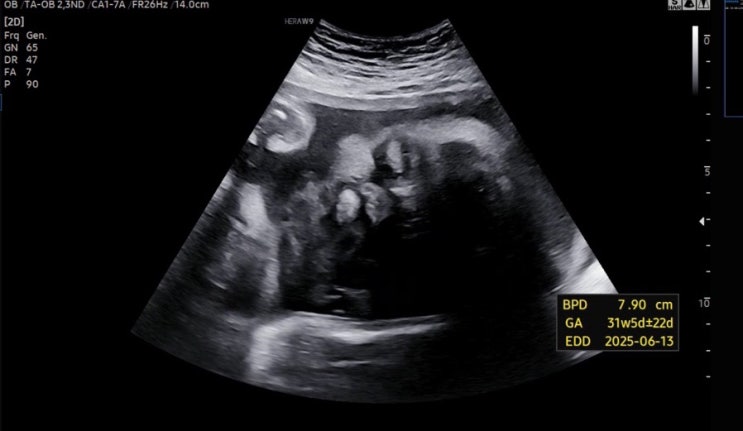

[젠또일기] 30주 ~ 31주 (아인병원 검진, 역아 탈출 !!!)

30주 ✔️ 30주 증상 1. 졸림과 불면증 ..? 사이 다시 잠이 많아진건지, 평일은 10시 전에 잠듬 근데 새벽...